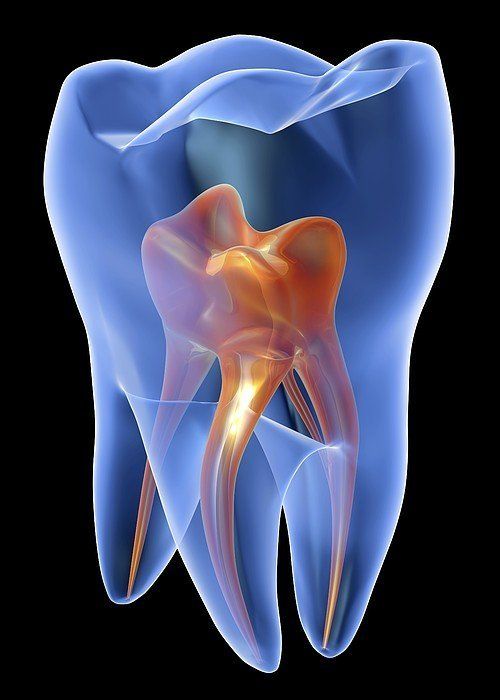

Ein Zahn ist aus mehreren unterschiedlichen Gewebeschichten aufgebaut. Die Zahnkrone ist vom Zahnschmelz, der härtesten Substanz im menschlichen Körper, überzogen. Darunter liegt als Hauptbestandteil des Zahns, das weniger harte Zahnbein. Diese auch als Dentin bezeichnete Substanz umschließt das Zahninnere, Der Zahnnerv (Pulpa) liegt in der nervenhöhle und im Wurzelkanal, enthält feinste Blutgefäße und Nerven, durchzieht den ganzen Zahn bis zur Wurzelspitze und ist hier in Verbindung mit dem Blutkreislauf.

Die Endodontie („im Zahn“) befasst sich als Teilgebiet der Zahnheilkunde mit dem Zahninneren, den Erkrankungen der Zahnpulpa. Zum Aufgabengebiet eines Endodontologen gehört die Behandlung „toter“ oder traumatisierter Zähne, Wurzelkanalbehandlungen sowie Wurzelspitzenresektionen. Wurzelkanalbehandlungen haben immer zum Ziel, den Zahnerhalt zu sichern.